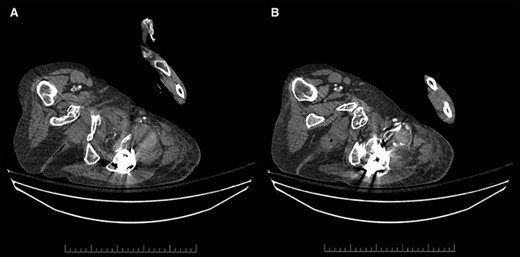

Contrast-enhanced arterial phase axial computed tomographic (CT) images overlying the left hip demonstrating (A) hyperdense material anterior to the left hip in keeping with hematoma (left), and (B) hyperdense material that corresponds to the pseudoaneurysm, which is supplied by a small DFA branch coursing anteriorly and abutting a sharp osseous fragment (right).

Unfortunately, due to increasing pain and difficulty weight-bearing, she presented to the emergency room on POD33. She was found to have new left thigh swelling and pain. Deep vein thrombosis (DVT) was ruled out with duplex ultrasound; however, a large left DFA pseudoaneurysm measuring 5.6 cm in length with a neck of 0.4 cm was visualized (Fig. 2). Computed tomography (CT) imaging confirmed a left DFA branch pseudoaneurysm with active extravasation, adjacent to a free-floating osseous fragment, associated with a large thigh hematoma (Fig. 3). In consultation with hematology, her apixaban was not reversed.